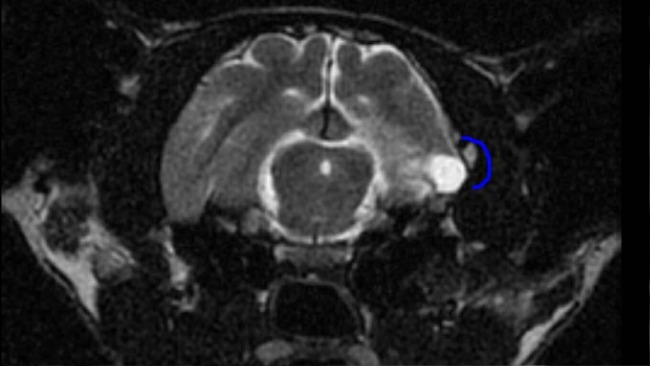

Tak Sonic trafił do dr Neurolog aż w Gdyni, która postawiła diagnozę: ogromny ropień, zakażenie bakteryjne, bardzo prawdopodobne ciało obce w główce i konieczność natychmiastowej operacji.

Sonic jest już po operacji. Z uwagi na nasilające się problemy z oddychaniem w trakcie, trzeba było podzielić ją na dwie części. Miał opłukane okolice puszki bębenkowej, pobrany wycinek do histopatologii, Sonic przeżył.